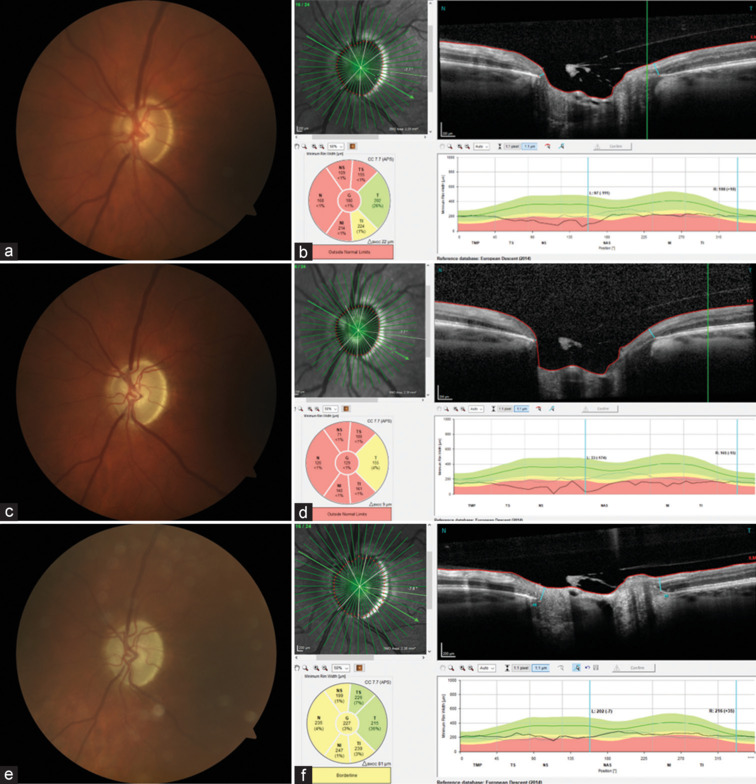

在这个病例系列中,我们报告了三个成人小梁切除术后视盘拔罐的逆转。2例患者术后出现无症状的低眼压(IOP),而第三例患者的间歇性IOP升高持续了一个月。通过视盘摄影和光谱域光学相干断层扫描(SD-OCT)成像证实了拔火罐的逆转,这在成人中很少见,增强了这些发现的客观性。尽管杯盘比(C/D)发生了这些变化,但所有患者的视野指数没有明显变化。这一系列是SD-OCT记录的成年人术后2年拔罐逆转的病例。

In this case series, we report the reversal of optic disc cupping in three adults following trabeculectomy. Two patients experienced asymptomatic low intraocular pressure (IOP) postoperatively, while the third patient had intermittently elevated IOP for a month. The reversal of cupping, a rare occurrence in adults, was confirmed through optic disc photography and the use of spectral domain-optical coherence tomography (SD-OCT) imaging, which enhances the objectivity of these findings. Despite these changes in cup-to-disc ratio (C/D), there were no significant changes in visual field indices in any of the patients. This series is SD-OCT documented cases of cupping reversal in adults up to 2 years postoperatively.